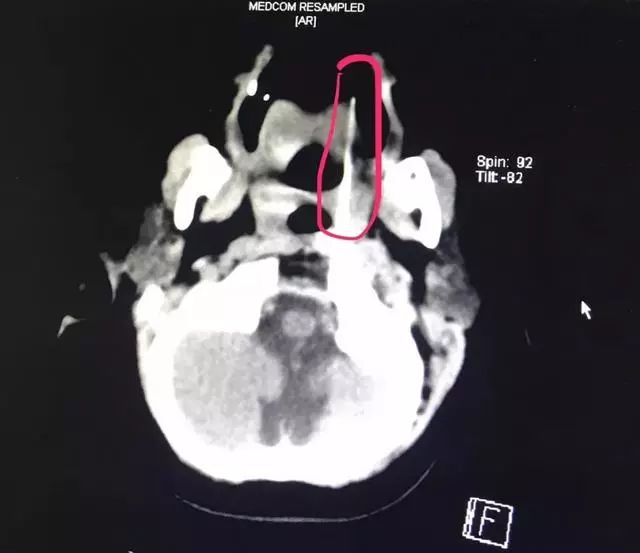

接诊的医护人员迅速为患儿安排了病床并实施了相关检查。CTA检查、颅脑CT、三维重建等一系列检查显示,长达13厘米的竹签经过小姑娘的口腔,直指环枢椎关节间隙,紧紧抵住人体最致命部位之一的椎动脉。

患儿的影像资料印证了医务部孔心涓主任的担心:

竹签刺入的部位极其特殊而凶险,如果竹签有一丁点挪动,可能会导致椎动脉被刺破,患儿就会有生命危险。